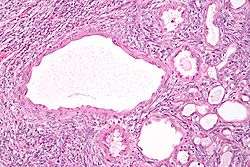

High magnification micrograph of a cystic nephroma showing the characteristic simple epithelium with hobnail morphology, and the ovarian-like stroma. H&E stain.

The characteristics of cystic nephromas are:

- Cysts lined by a simple epithelium with a hobnail morphology, i.e. the nuclei of the cyst lining epithelium bulges into the lumen of the cysts,

- Ovarian-like stroma that has a:

- Spindle cell morphology, and has a

- Basophilic cytoplasm.

Micrograph of a cystic nephroma. H&E stain.